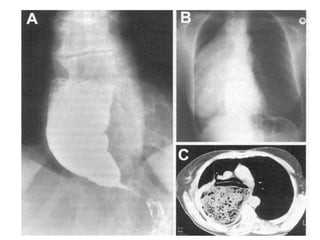

Tipos de hérnias:

tipo I, de deslizamento (fraqueza da membrana freno-esofágica)

tipo II, paraesofágica

tipo III, mista.

Quando o EEI no tórax a pressão é mais baixa..

Doentes com hérnia do hiato assintomática:

sem necessidade de tratamento.

Hérnias paraesofágicas

Tipo II e III

Fisiopatologia.

Risco de estrangulamento parece ser baixo.

Sintomas: dor e azia (50%), hemorragia (30%)

Diagnóstico:

Trânsito esofágico

Manometria

Ph metria

Tratamento